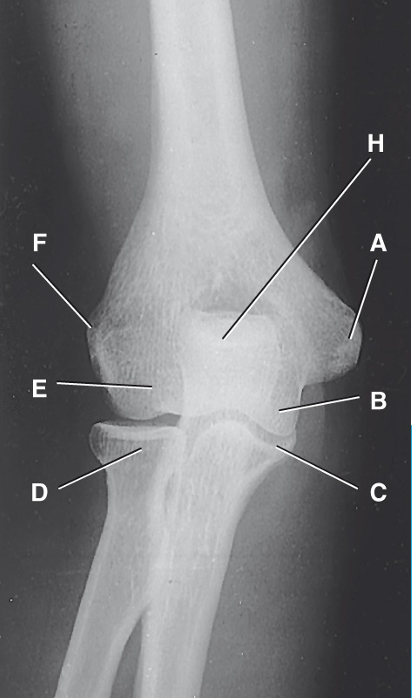

6

Q

What type of synovial joint is this

A

Ginglymus (hinge)